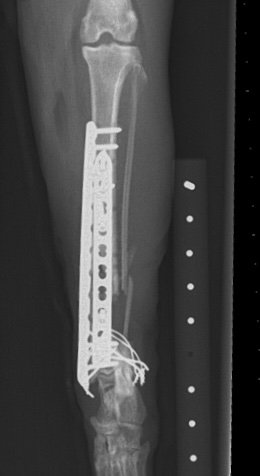

What would you do with this :-0 Our autumn meeting is all about...REVISION SURGERY! 20-22nd Nov in Bristol, full details and booking info shared here v soon :-)

What would you do with this :-0

Our autumn meeting is all about...REVISION SURGERY!

20-22nd Nov in Bristol, full details and booking info shared here v soon :-)